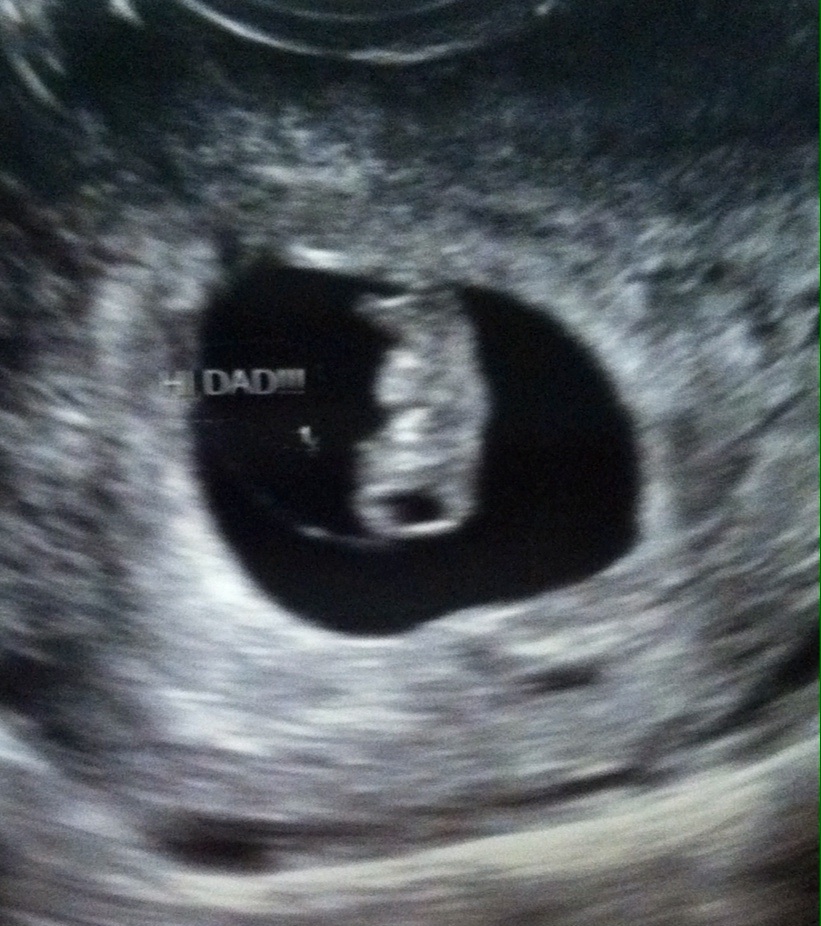

Woke up this morning with a tiny amount of brown spotting. Since I've miscarried before, I decided to call my dr and they were able to squeeze me in for an ultrasound early this AM. Low and behold a baby measuring exactly 6 weeks, 6 days which is where it should be. They saw a heartbeat too! I'm so overjoyed, and am celebrating that I am pregnant TODAY and trying to not think too much about the future. Bleeding has since stopped. She said could have been from intercourse or heavy lifting. Here's our bean: